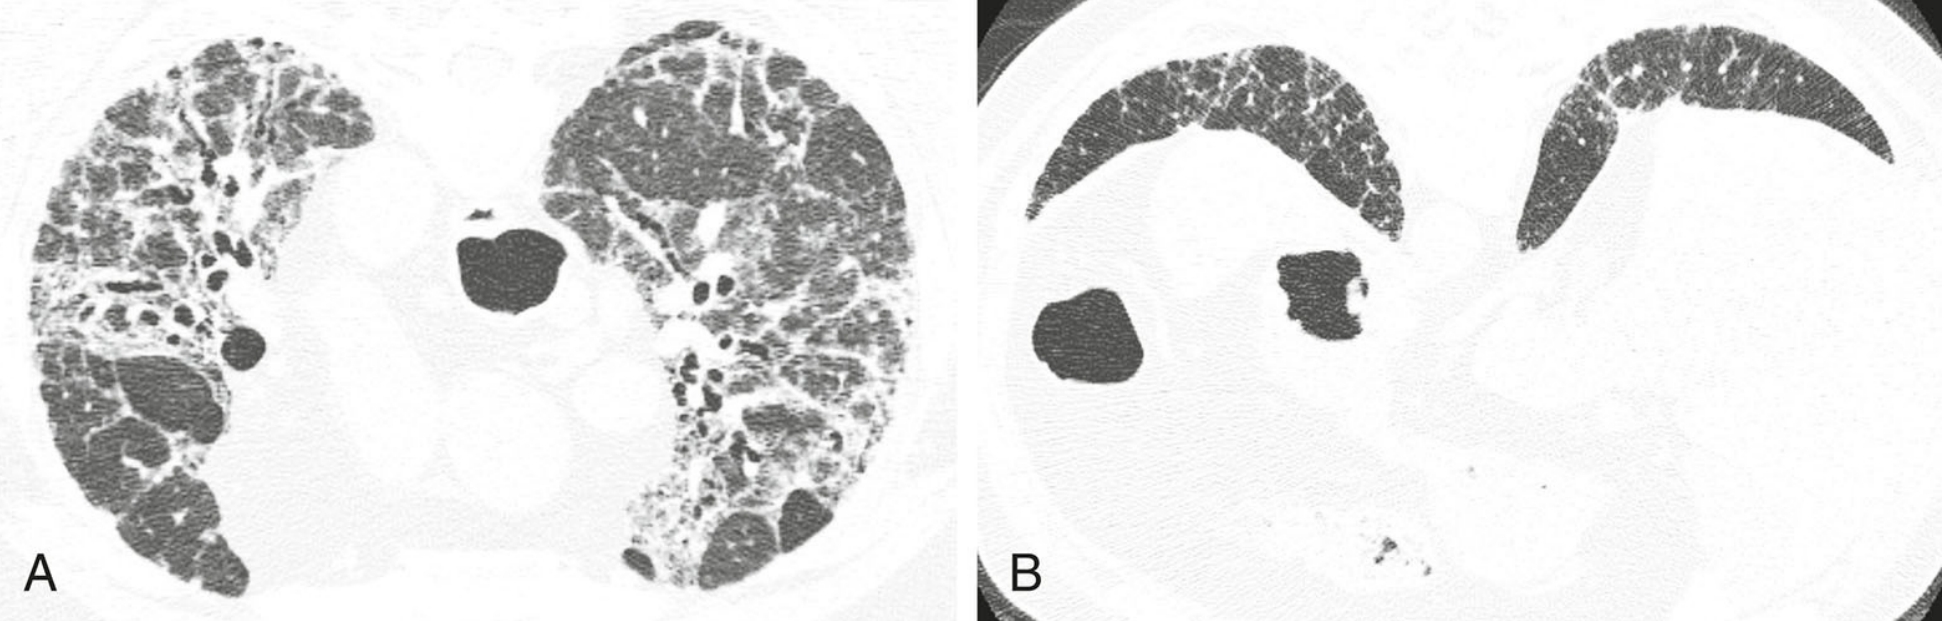

7331218b6857cead2350daf293806044.png

高置信度诊断为普通型间质性肺炎(UIP)的鉴别诊断。

4例UIP的HRCT表现;继发于特发性肺纤维化(A)、结缔组织病(B)、石棉沉着病(C)和药物中毒(D)的UIP, 均可见胸膜下及肺基底分布为主的纤维化伴蜂窝征。当表现为UIP模式时,上述疾病在HRCT上通常无法鉴别。